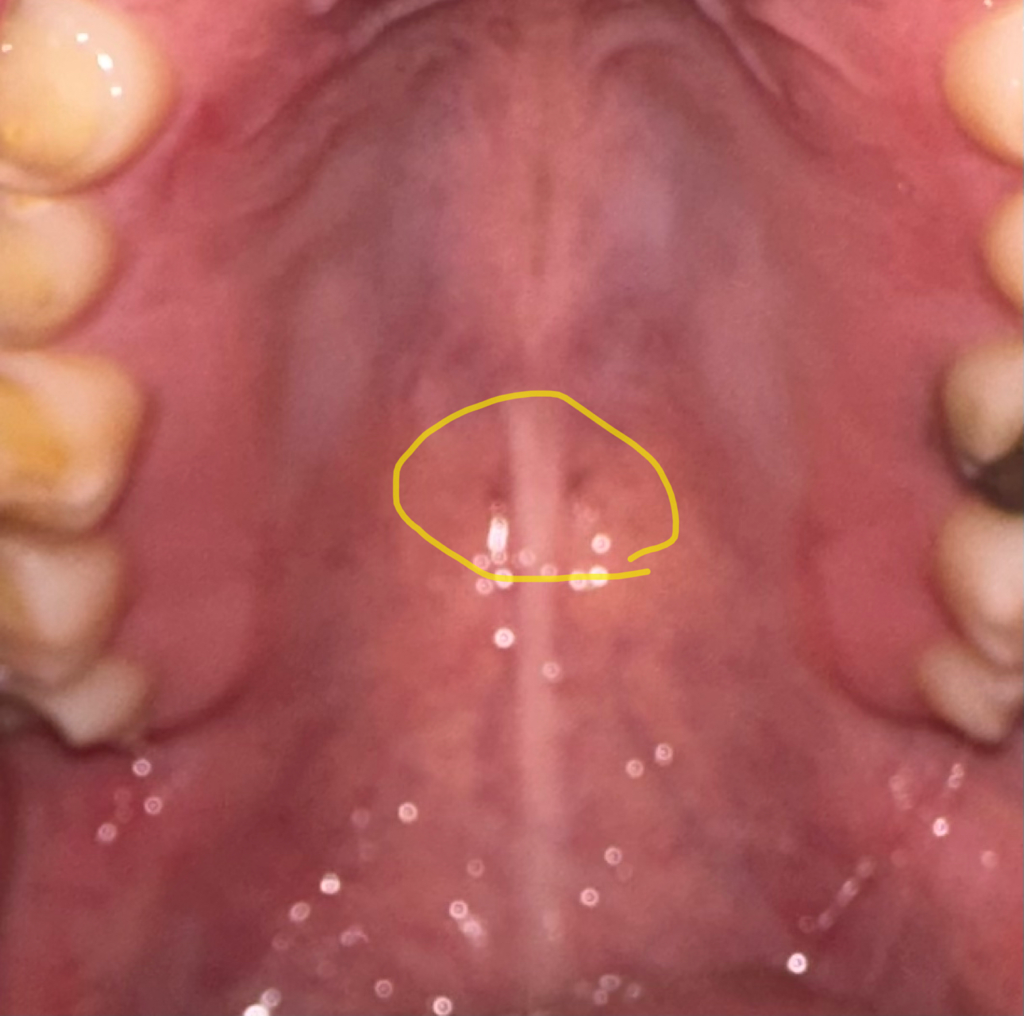

그래서 조금 전 휴대폰 후레쉬로 제 입속을 들여다봤는데 사진과 같이 입천장에 검정색 점이 대칭으로 두개씩이나 있어서 혹시나 구강암의 증상이 아닐까 싶어 질문 남깁니다.

통증은 없으나 구강암을 비롯한 두경부암 증상이 사진처럼 구강(입천장)에 검정색 점이 나타나는 양상을 보이기도 하나요?

• 1번 째 사진

점이라고 표현 하긴 했지만 원래 있는 구멍입니다.

해부학적으로 이상이 없는것이니 걱정하지 않고 지내셔도 됩니다.

대칭적이라면 혈관 등이 점막에 의해 비치는 것일 가능성이 있습니다.

암의 가능성은 매우 낮습니다. 하지만 걱정이 되신다면 이비인후과 등에서 정확한 진단을 받아보시는 것이 좋겠습니다.